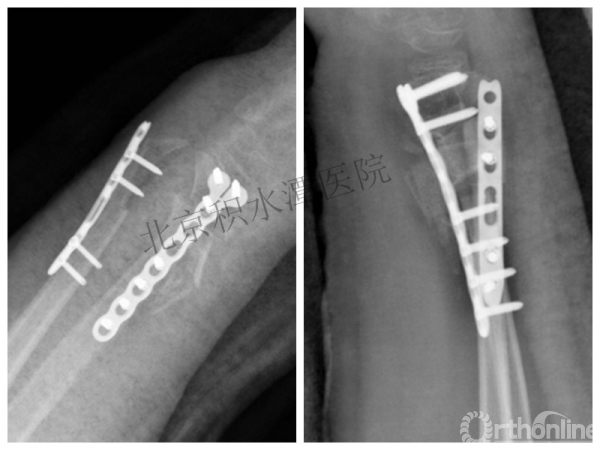

病例分享六

7岁、男孩,桡骨远端骨折

医生的处理方法!——医生终于没有坚持自己的原则!

伤后40天—切开复位内固定!

手术历时近 5小时!心情之压抑无以言表!因为当时的经治医生是他们的进修生!感觉是他们的失职甚至渎职!

唯一可以肯定—预后不佳!郭教授是党员!是无神论者!但是很诡异的事情:手术中发生—C形臂看不清!拍片条件总是调节不好!手术器械换了三套!内固定钢板总不合适!

术后15月,虽然家长满意了,但是他们医生不满意!